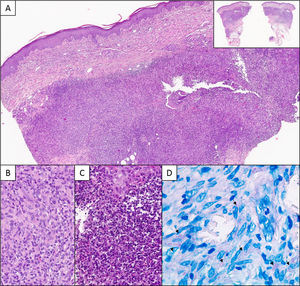

A. Corte histológico que muestra un infiltrado dérmico profundo granulomatoso de patrón nodular (detalle panorámico en la esquina superior derecha) (H-E 40×). B. Detalle del infiltrado, constituido por linfocitos e histiocitos (H-E 200×). C. Áreas supurativas con abundantes neutrófilos y restos celulares (H-E 400×) D. Técnica histoquímica de Ziehl-Neelsen. Flechas señalando estructuras alargadas de color rosa (630×).

La biopsia es fundamental para el diagnóstico. Histopatológicamente se pueden encontrar diferentes patrones entre los que destacan un infiltrado difuso de histiocitos, microabscesos, paniculitis, granulomas tuberculoides o sarcoideos y/o vasculopatía reactiva9. Los bacilos ácido alcohol resistentes se evidencian mediante tinciones específicas como Ziehl-Neelsen, aunque un resultado negativo no descarta una micobacteriosis5,10. El diagnóstico se confirma mediante el cultivo o con técnicas moleculares como la PCR-RFLP2,10.